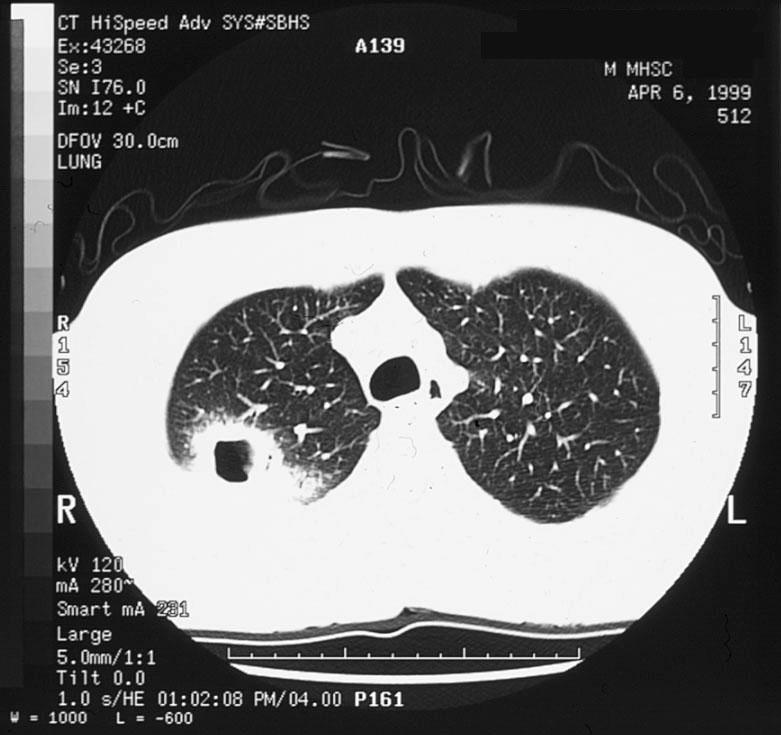

胸部CT可以评估肺炎、肺脓肿、肿瘤、胸腔积液其他胸膜疾病或胸膜增厚。与胸部X线相比,胸部CT对肺部感染的敏感性增加,特别是对免疫功能低下的患者。当X线片检查结果阴性,但对重大肺部感染的怀疑指数很高时,可以考虑进行胸部CT检查

。

下图为成年患者的肺脓肿

图9 患者男,42岁,发热并痰液恶臭。有大量饮酒史,体格检查牙列很差。胸部X线片显示右上叶后段肺脓肿。CT扫描显示一个薄壁空洞,周围有实变。